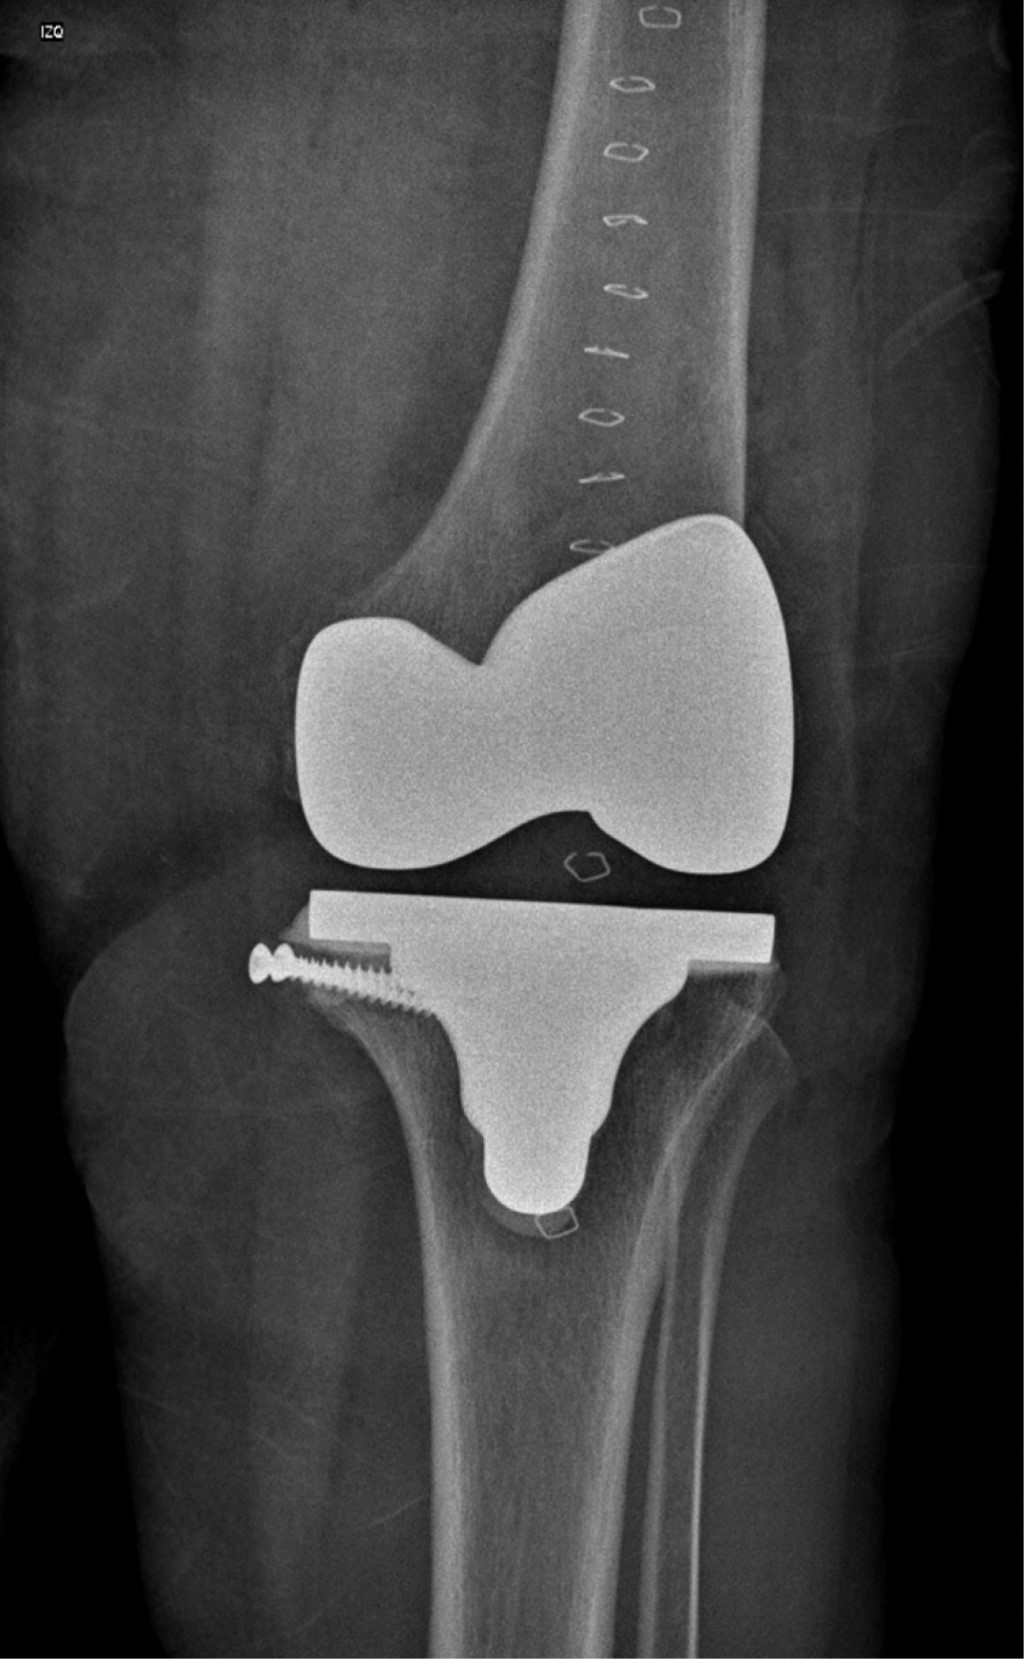

Se presenta caso de mujer de 62 años, dedicada al cuidado del hogar, con antecedente de presbiacusia, la cual acude a consulta externa por gonalgia bilateral, de predominio izquierdo, de siete años de evolución. A la exploración física se aprecia franca deformidad en varo en ambas rodillas (Figura 1), de mayor magnitud en lado izquierdo, con marcha independiente asistida con bastón, rango de movilidad activo con extensión de -5o, flexión de 85o, Ficat y cepillos positivos, cajones negativos y bostezo medial positivo, con limitación por dolor para las actividades de la vida diaria y dolor en EVA de 8. Se solicitan y revisan radiografías anteroposterior (Figura 2) y lateral (Figura 3) de ambas rodillas en bipedestación, encontrando gonartrosis bilateral Kellgreen & Lawrence IV, con defecto tibial medial en rodilla izquierda, por lo cual se le propone tratamiento quirúrgico con artroplastia total de rodilla izquierda posteroestabilizada, debido a la mayor sintomatología en dicho lado.

La paciente es egresada al día siguiente de procedimiento quirúrgico con indicación de mantener extremidad pélvica izquierda en descarga hasta encontrar datos radiográficos de consolidación en injerto, y se cita a revisión a los siete, 14 y 28 días después del procedimiento (Figuras 8 y 9).

En el caso aquí reportado, se utilizó injerto autólogo proveniente del corte de chaflán anterior femoral para la reconstrucción tibial medial, el cual se fijó con tornillos de esponjosa de 4.0 mm, sin encontrar datos de reabsorción, aflojamiento o fragmentación en un seguimiento temprano de ocho semanas, con mejoría significativa de sintomatología y aumento de funcionalidad (Figuras 10, 11 y 12).

Figura 2

Figura 3

Figura 7

Figura 8

Figura 9

Figura 10

Figura 11

Figura 12